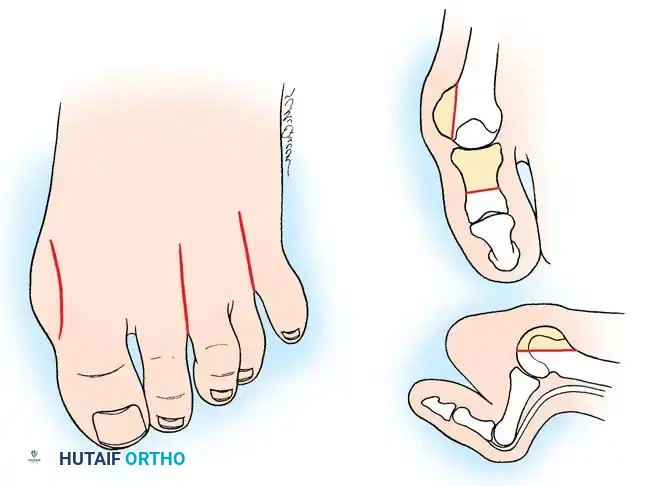

Step 3: Lesser Metatarsal Head Resection

- Approach: Two dorsal longitudinal incisions are typically utilized (one centered between the 2nd and 3rd rays, and one between the 4th and 5th rays) to access all lesser MTP joints while preserving dorsal skin bridges. Alternatively, a transverse plantar approach can be used if severe plantar callosities require excision.

- Resection: The extensor tendons are retracted or lengthened (Z-plasty). The dorsal capsule is opened, and the collateral ligaments are sharply divided to allow plantarflexion of the metatarsal.

- Osteotomy: An oscillating saw is used to resect the metatarsal heads at the anatomical neck. It is imperative to create a smooth, parabolic cascade (the 2nd metatarsal should be the longest, tapering down to the 5th).

- Soft Tissue Balancing: The plantar plate and fat pad, which have migrated distally, are mobilized and pulled proximally under the remaining metatarsal stumps. If the toes remain contracted, closed osteoclasis or PIP joint resection arthroplasties may be performed.

- Pinning: Smooth Kirschner wires (K-wires) are driven antegrade through the toes and retrograde into the metatarsal shafts to hold the toes in neutral alignment.

Intraoperative view demonstrating the exposure and resection of the lesser metatarsal heads to decompress the forefoot and allow reduction of the dislocated digits.